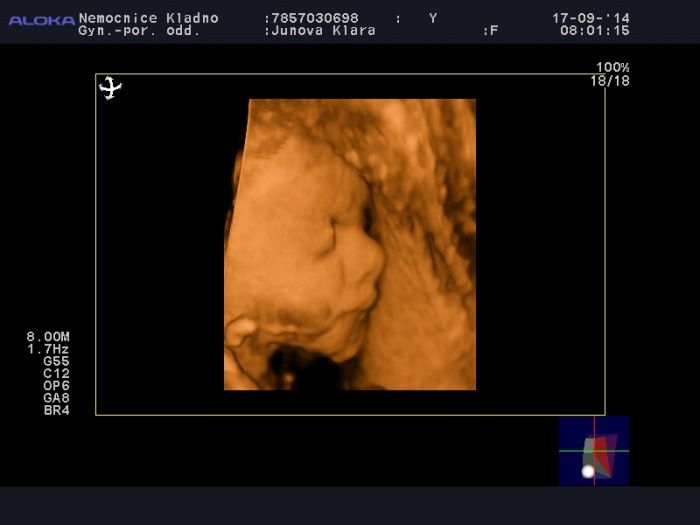

Jo a ten 3D ultrazvuk malého je úžasný